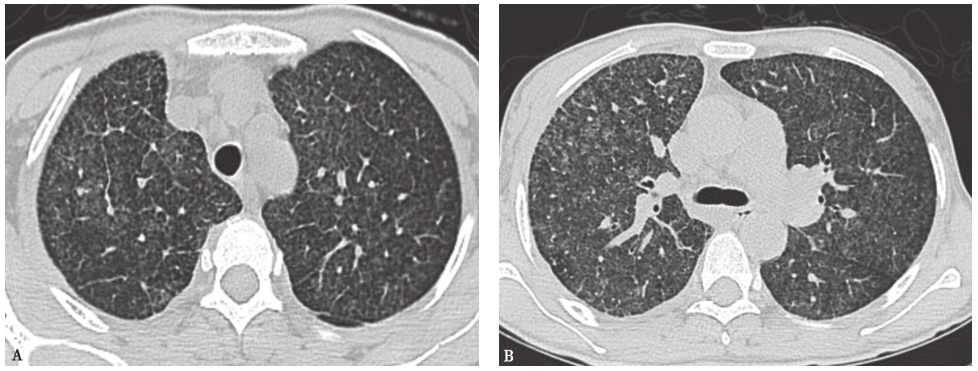

17个月前胸部CT见双肺弥漫性小结节(图1)。

图1 17个月前胸部CT表现